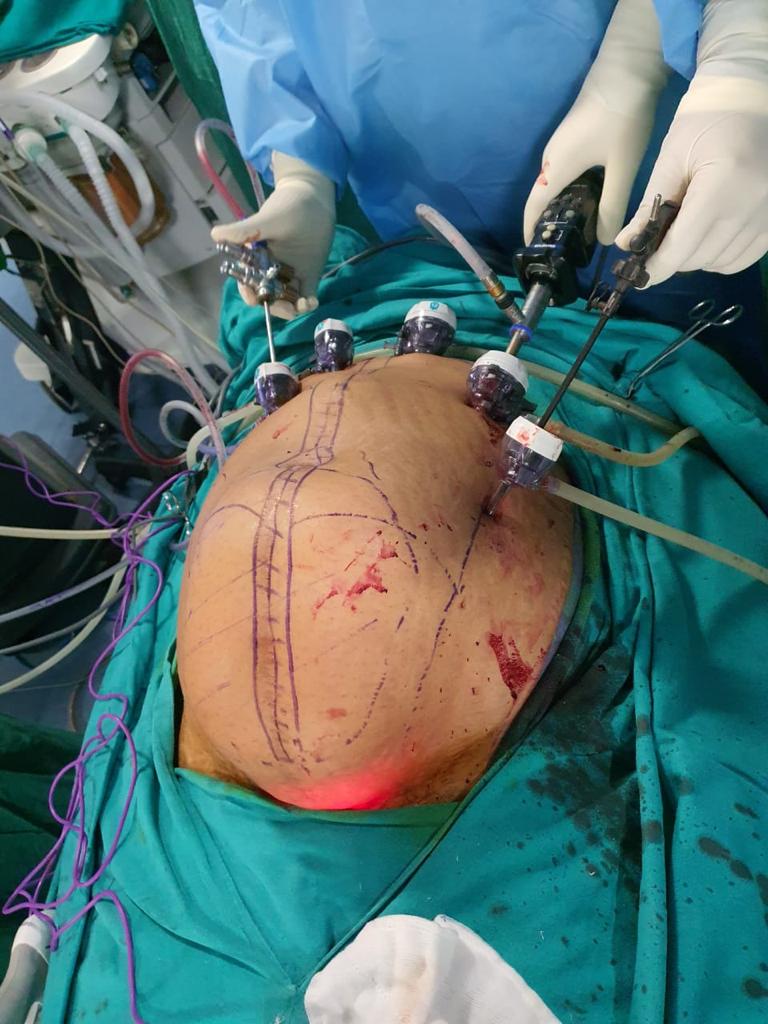

Complex abdominal wall ventral hernia done completely done Laparoscopically ( e-TEP/ RS/ UL TAR )